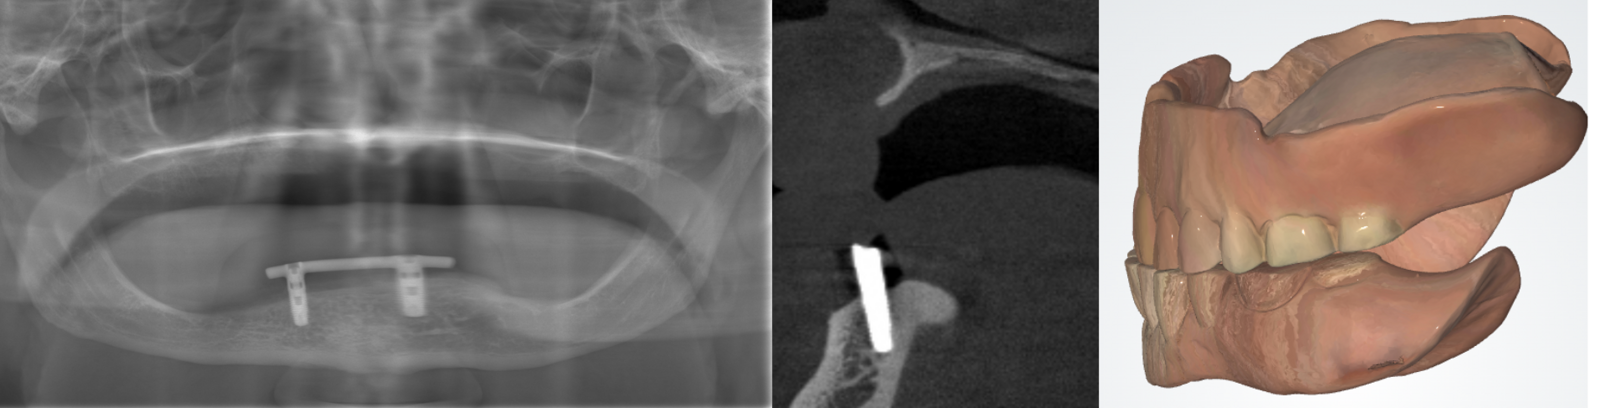

CBCT wordt internationaal beschouwd als de gouden standaard voor preoperatieve beoordeling van ernstig geslonken kaken3-4, ondersteund door SedentexCT-richtlijnen betreffende objectieve classificatie van kaakatrofie en planning van implantaten.5 De indicatie geldt bij twijfel over hoogte, breedte of morfologie van de kaak bij het vermoeden van ernstige kaakatrofie, waarbij nauwkeurige beoordeling cruciaal is voor implantaatplaatsing.6 Met CBCT kunnen exacte metingen van hoogte en breedte worden vastgesteld. CBCT is gerechtvaardigd bij twijfel over botvolume, complexe anatomie of digitale implantaatplanning (figuur 2).

Een voorbeeld van een volledige prothese met versleten elementen en ernstige resorptie van de proc. alveolaris (knife edge) in de bovenkaak tegen een steg-ondersteunde overkappingsprothese. De mate van de resorptie is slechts op de CBCT-scan vast te stellen.

In de SedentexCT-richtlijnen wordt gesteld: ‟CBCT should only be used when conventional radiography cannot provide sufficient information for diagnosis or treatment planning. In the assessment of severely atrophic jaws, CBCT provides essential 3D information on alveolar height and width, enabling precise implant planning while minimizing risk to anatomical structures."14